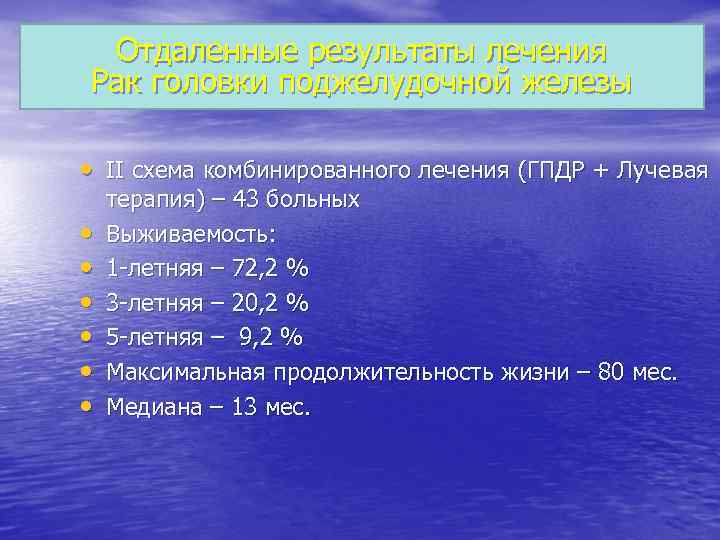

Отдаленные результаты лечения Рак головки поджелудочной железы • II схема комбинированного лечения (ГПДР + Лучевая • • • терапия) – 43 больных Выживаемость: 1 -летняя – 72, 2 % 3 -летняя – 20, 2 % 5 -летняя – 9, 2 % Максимальная продолжительность жизни – 80 мес. Медиана – 13 мес.